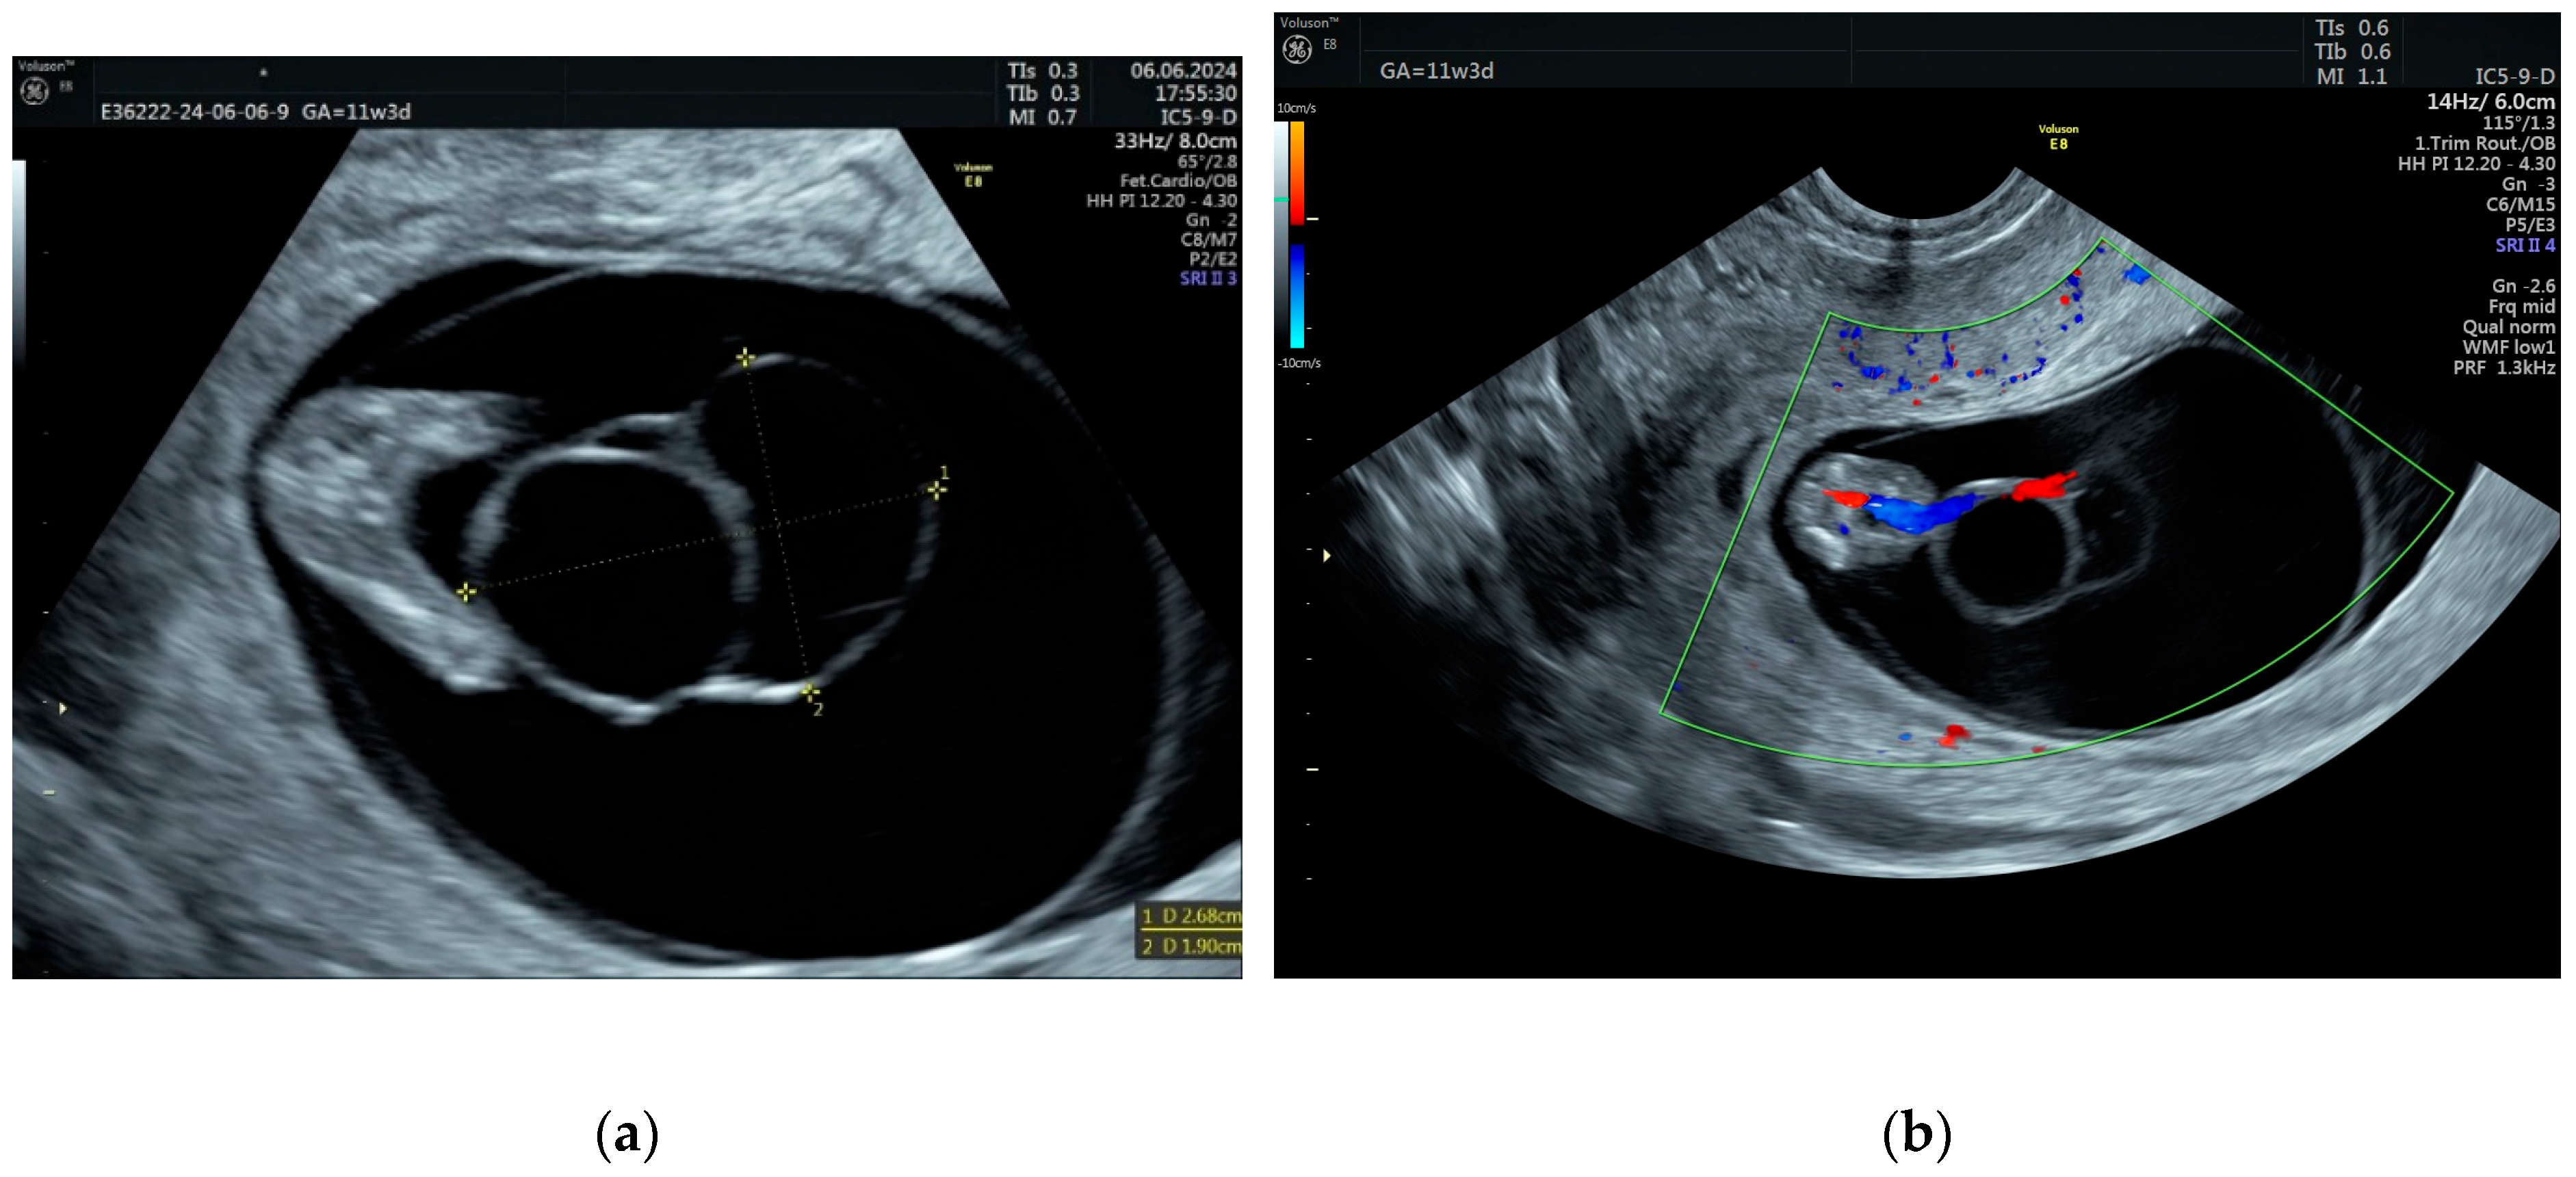

3.1. Case Report